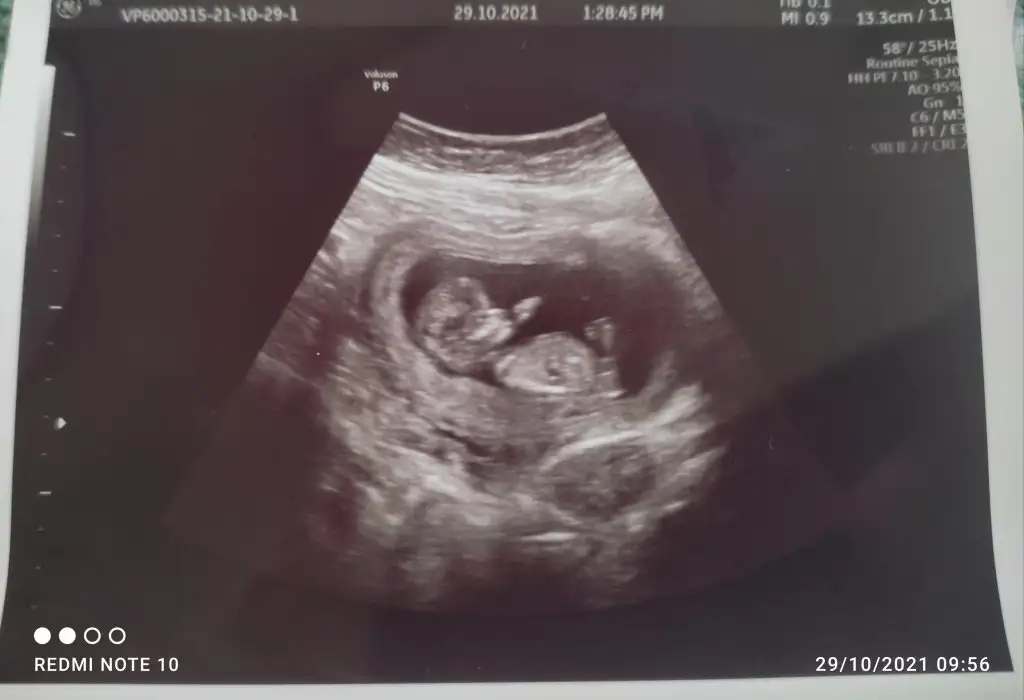

Erkek görünüyorMerhabaIkra meyra 9 haftalıkken fotoğrafını paylaşmıştım ancak 12 de daha net belli olur demiştin şuan 12+3 günlük var mı bir tahminin ?

![]()